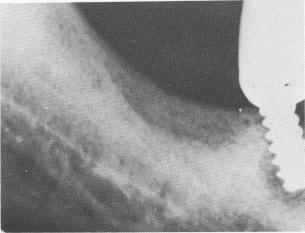

Fig. 14-17. A Lew screw failing for several reasons: the implant was not set parallel to the remaining teeth, and since it was distally tipped, the forces brought to bear upon it caused the distal proximal surface of the bone to resorb. The trephining may have been made larger than the screw threads. The neck is not reduced.

2 Lew screw failing for several reasons in mandible